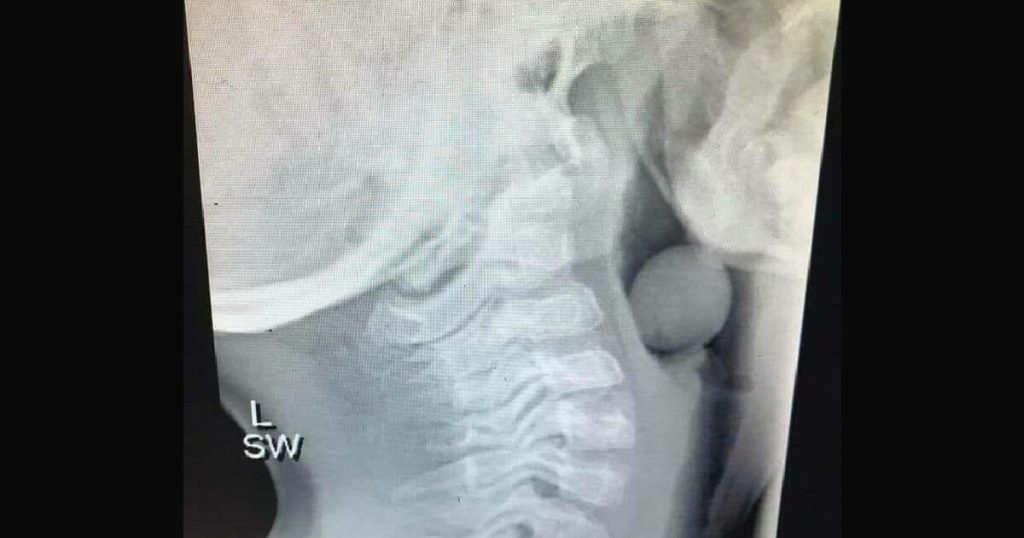

X-ray of child’s throat highlights importance of choking hazard safety